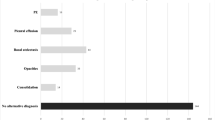

The mean age of the pregnant group (n = 40) was 33 years old (SD 5.4, range 22 to 44 old). The pregnant women were on average 27 weeks pregnant (SD 8.2, range 6 to 40 weeks) at the time of their CTPA examinations. None of the pregnant women had a background of chronic cardio-respiratory disease, and they were previously fit and healthy. The mean age of the non-pregnant group (n = 40) was 30 years old (SD 7.1, range 18 to 40 years old). None of the CTPA studies in the pregnant women was positive for PE compared to two positive studies (5.0%) for the non-pregnant group. Six studies in the pregnant group showed evidence of consolidation compared to five studies in the non-pregnant group. Moreover, one study in a pregnant woman showed evidence of a moderate pleural effusion, the cause of which was unclear.

Differences between overall study quality between the pregnant and non-pregnant group are summarised in Fig. 1. The percentage of sub-optimal cases (defined as grade 2 or less) was more than three times higher in the pregnant group [27.5%, (11/40)] compared with the non-pregnant group [7.5%, (3/40)]; this was statistically significant (p = 0.015).

Out of the total of 920 vascular segments evaluated for each group, the percentage of segments with inadequate opacification to confidently exclude pulmonary emboli (i.e., with a subjective score of 3 or less), was more than two times higher in the pregnant group [28.7% (264/920)] than in the non-pregnant group [13.3% (122/920)]; this difference was statistically significant (p = 0.0001).

Our study highlights a different aspect of the debate regarding the choice of first-line modality in pregnancy. We have conclusively shown that the incidence of sub-optimal CTPA studies is much higher in pregnant patients (27.5%) compared to non-pregnant patients (7.5%). The proportion of sub-optimal studies in our control group is in keeping with rates of 5–10% of non-diagnostic studies quoted in non-pregnant patients in the literature [13]. Moreover, we have shown that the degree of contrast enhancement was consistently better, both subjectively and objectively, in CTPA studies performed in non-pregnant patients compared with pregnant patients, at every level from the main pulmonary artery to sixth order arteries. Motion artefacts were also worse in studies in pregnant compared to non-pregnant patients. The reasons behind the difference in motion artefacts are unclear, but it is possible that pregnant women had more difficulty in suspending breathing. The implications of a sub-optimal CTPA study are clearly that a definitive diagnosis sometimes cannot be made, so that repeat imaging may be necessary, incurring the costs of further radiation dose to both mother and foetus.